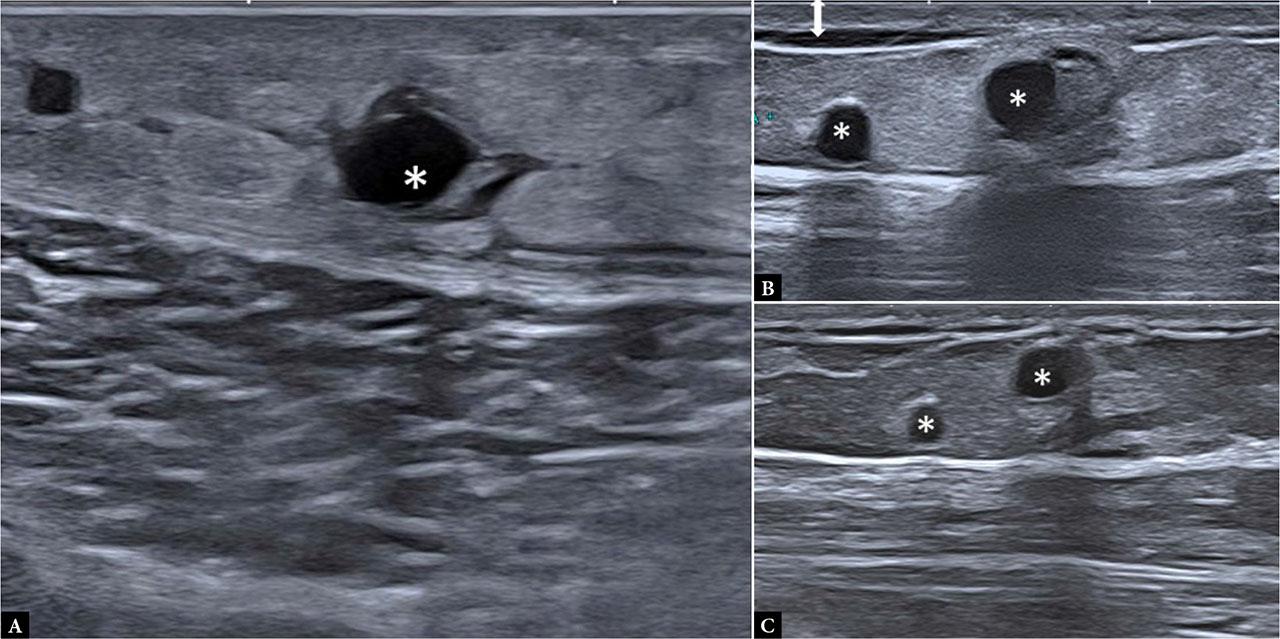

In the acute phase, blunt trauma panniculitis is visualized as an area of lobular panniculitis sonographic pattern beneath the contused skin. These lesions tend to be triangular, with the base at the skin surface. When compression occurs between the bone and a hard object, deeper involvement of the SAT, adjacent to bone, is common. Small spherical seromas are frequently observed within the affected region and tend to persist longer than areas of increased echogenicity (Fig. 6).

Blunt trauma panniculitis. Evolution after acute blunt trauma at the lateral aspect of the arm: A. Two days after trauma: predominantly lobular panniculitis sonographic pattern and round cysts (*); B. Four weeks later: decrease in the hyperechoic area and normalization of superficial hypodermal and dermal echogenicity; C. Three months after trauma: subtle hyperechogenicity around persistent cysts